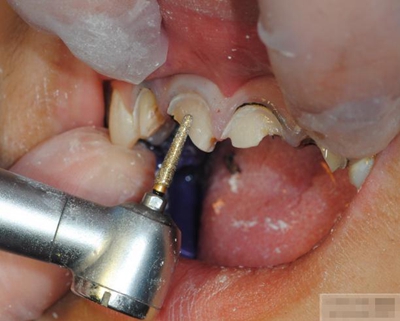

選擇合適的完成鉆制備根管,

通常深入到根管的1/2至2/3處

【纖維樁制作】

修整纖維樁長度

取出纖維樁,按所需長度裁截纖維樁 在有水條件下 用切割砂片或車針截取纖維樁,切勿使用鉗子,剪刀或鑷子以免破壞樁的結(jié)構(gòu)

涂布硅烷偶聯(lián)劑

涂布粘接劑

將樹脂粘接劑均勻涂抹在根管、牙體的粘接面以及纖維樁表面,涂抹兩遍

粘接

將調(diào)好的樹脂水門汀用口內(nèi)注射頭送入根管

將纖維樁表面涂滿調(diào)好的樹脂水門汀,安放在根管內(nèi)就位,保持壓力10秒